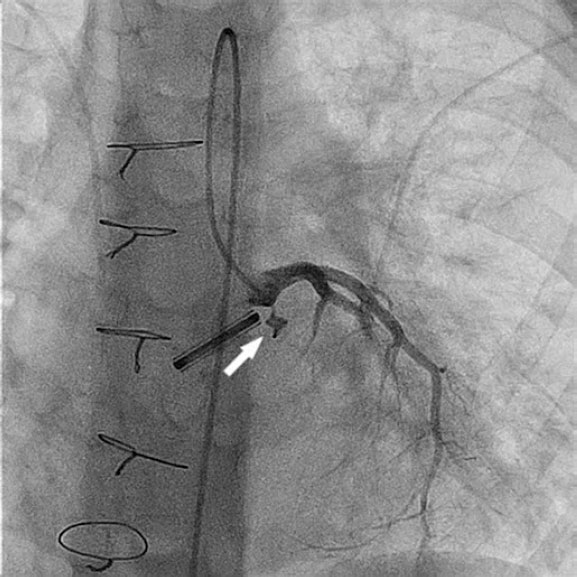

Se sondó la fístula con un catéter NIH 4F modificado (Cordis, Estados Unidos) y una guía hidrófila de 0,035 pulgadas sobre la que se avanzó un catéter de liberación de 4Fr para implantar un dispositivo Nit-Occlud PDA 4 × 4 mm (PFM Medical, Alemania) (figura 2 y vídeo S2). Se eligió este dispositivo en lugar de oclusores de malla de nitinol porque se consideró que la longitud de estos últimos era excesiva y que sus discos de retención podían interferir con la coronaria.

Figura 2.